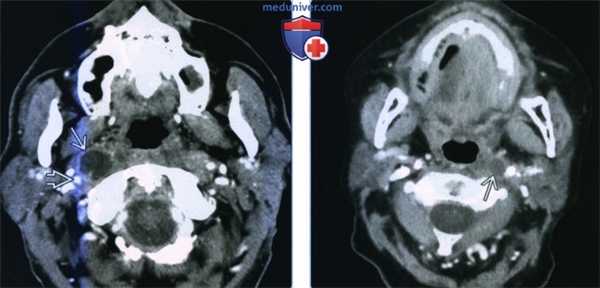

(Слева) КТ с КУ, аксиальный срез на уровне носоглотки. В латеральном отделе заглоточного пространства, медиальнее правой внутренней сонной артерии визуализируется крупный некротизированный лимфоузел. У взрослых при подозрении на злокачественное поражение лимфатических узлов наиболее вероятной причиной является плоскоклеточный рак глотки.

(Справа) КТ с КУ, аксиальная проекция, пациент с плоскоклеточным раком ротоглотки. Метастатическое поражение левого заглоточного лимфоузла, которое привело к его кистозному перерождению. При проведении ПЭТ захвата ФДГ не наблюдалось. Кистозные лимфоузлы могут стать причиной ложноположительных результатов при проведении ПЭТ.